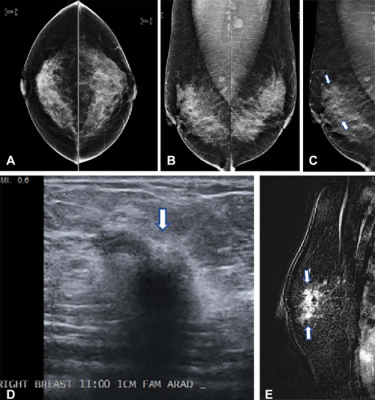

Images in a 42-year-old woman who presented for routine screening. (A) Two-dimensional craniocaudal digital mammogram and (B) two-dimensional mediolateral digital mammogram show heterogeneously dense breast tissue with no abnormality. (C) Mediolateral digital breast tomosynthesis image shows subtle architectural distortion (arrows) extending superiorly from the nipple level. (D) Target US image of the right breast shows a highly suspicious, hypoechoic, irregular mass (arrow). US-guided core biopsy yielded invasive ductal carcinoma with extensive ductal carcinoma in situ (T2N0M0; estrogen receptor–positive, progesterone receptor–positive, and human epidermal growth factor receptor 2–negative). (E) Right-breast MRI scan acquired to evaluate the extent of disease shows a clip artifact in the superior aspect of the irregular enhancing mass (arrows). No other suspicious lesions were seen. Image courtesy of RSNA